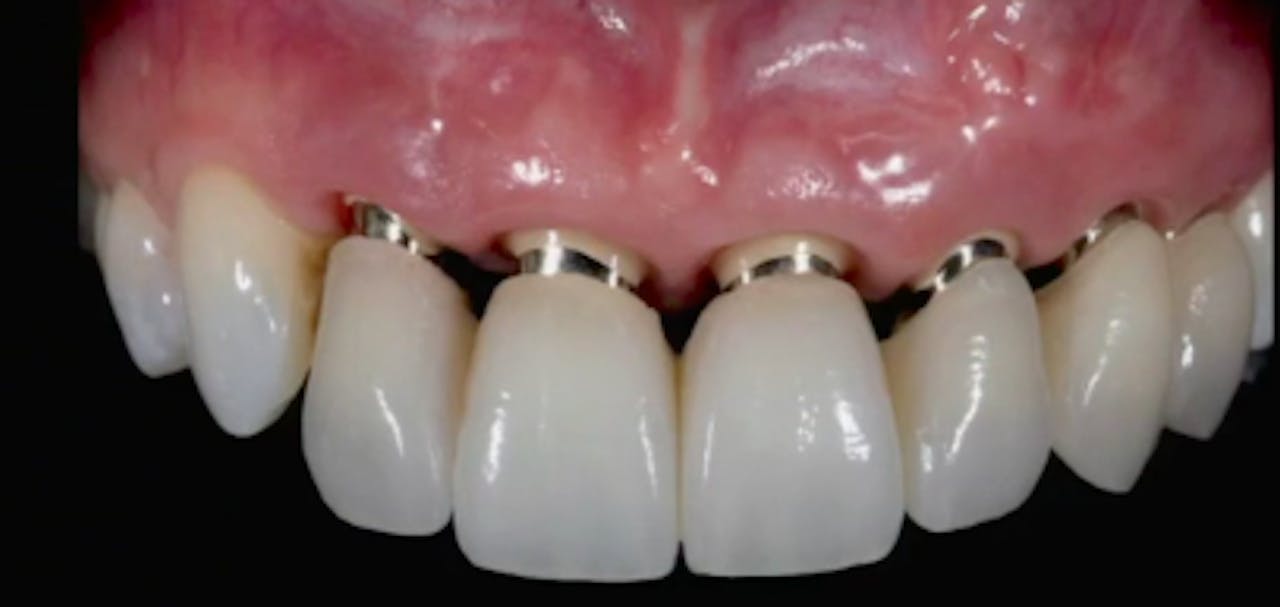

CLINICAL VIDEO Final implant restorative treatment using Procera crown Gide Dental Reviews 31,762 likes · 74 talking about this · 887 were. • 550+ clinical videos on web and app • new dental videos added. Read 26 customer reviews of gide dental center, one of the best. Premiere provider of online dental education. Clinical videos, expert interviews, live broadcasts over. Gide dental | 280 followers on linkedin. Learn from the world's most. Gide Dental Reviews.